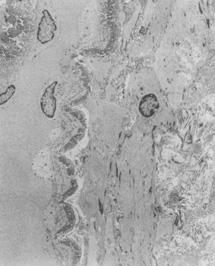

Ultrastructural studies show that developmental events of the sclera begin in the region anterior to the equator at approximately day 43.4,5 The late mesenchymal cells or very early fibroblasts of the anterior portion possess elongated nuclei and many glycogen granules and lipid vacuoles whereas those of the posterior portion possess round-to-oval nuclei and few glycogen granules and lipid vacuoles. The late mesenchymal cells or very early fibroblasts of the anterior and posterior portions contain many free ribosomes and polyribosomes, as well as immature rough-surfaced endoplasmic reticulum and Golgi complex. The early fibroblasts begin the synthesis of glycoproteins, glycosaminoglycans (especially hyaluronic acid), collagen, and elastin between day 43 and 50, thus filling the intercellular space. Developmental events directed from inside outward begin at week 7.2 with a marked increase in the inner portion in glycogen granules and lipid droplets of the cells, and in number and average diameter of collagen fibrils. Cytodevelopment of the sclera is characterized by decrease of ribosomes, polyribosomes, glycogen granules, and lipid vacuoles, and by increase of rough-surfaced endoplasmic reticulum and Golgi complex components. Development of intercellular substances is characterized by an increase in the number and average diameter of collagen fibrils (Fig. 1) and in the amount of elastic deposits with electron-translucent central cores. By week 10.9 there are no more differences between the inner and outer portions. By week 13 there are no more differences between the anterior and posterior portions. By week 24, fetal sclera has the same ultrastructural characteristics as adult sclera. Between week 6 and week 24 there is a threefold increase in thickness, possibly by progressive laying down of collagen fibrils on its inner aspect as more mature collagen fibrils are found in the outer part of the sclera and the younger smaller collagen fibrils on its inner aspect; thereafter the rate of increase diminishes rapidly.

Fig. 1. Transmission electron micrographs (x4000) of fetal sclera, week 16 of development (A), and adult sclera (B). Fetal sclera shows more fibroblasts and less packed and dense, intermingled arrangements of collagen bundless than adult sclera.